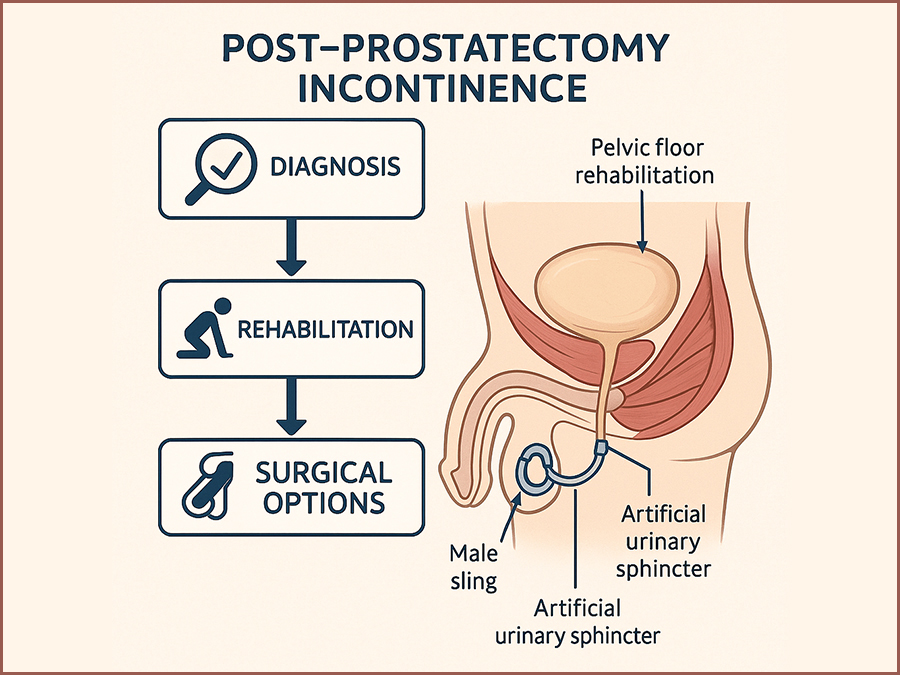

Post-Prostatectomy Incontinence: Risk Factors, Rehabilitation, and Surgical Options

SurgeryRadical prostatectomy is a cornerstone of curative therapy for localized prostate cancer, offering favorable oncologic outcomes in appropriately selected patients. However, one of its most common and distressing complications is post-prostatectomy incontinence (PPI), with reported rates ranging from 4% to 40% depending on the definition used, the surgical technique, and the timing of assessment. (1,2) This complication significantly impacts health-related quality of life, causing physical discomfort, emotional distress, and social withdrawal.(3) PPI differs from other types of male urinary incontinence in both etiology and management. It primarily results from iatrogenic damage to the sphincteric mechanism during prostate removal, although additional contributing factors include detrusor overactivity, impaired compliance, and changes in bladder neck dynamics.(4,5) Despite advancements in minimally invasive and robotic-assisted surgical approaches, PPI remains a challenge for both patients and clinicians. A comprehensive understanding of the pathophysiology and risk factors for PPI is essential to develop optimal prevention and management strategies. In addition, clinicians must be well-versed in both non-surgical and surgical treatment modalities to tailor therapy to individual patient needs and expectations.(6,7) This review aims to synthesize the current evidence on PPI, focusing on identifiable risk factors, effective rehabilitative strategies, and available surgical treatments. By consolidating contemporary research and clinical guidelines, this paper seeks to provide a clear framework for the management of PPI in urologic practice.